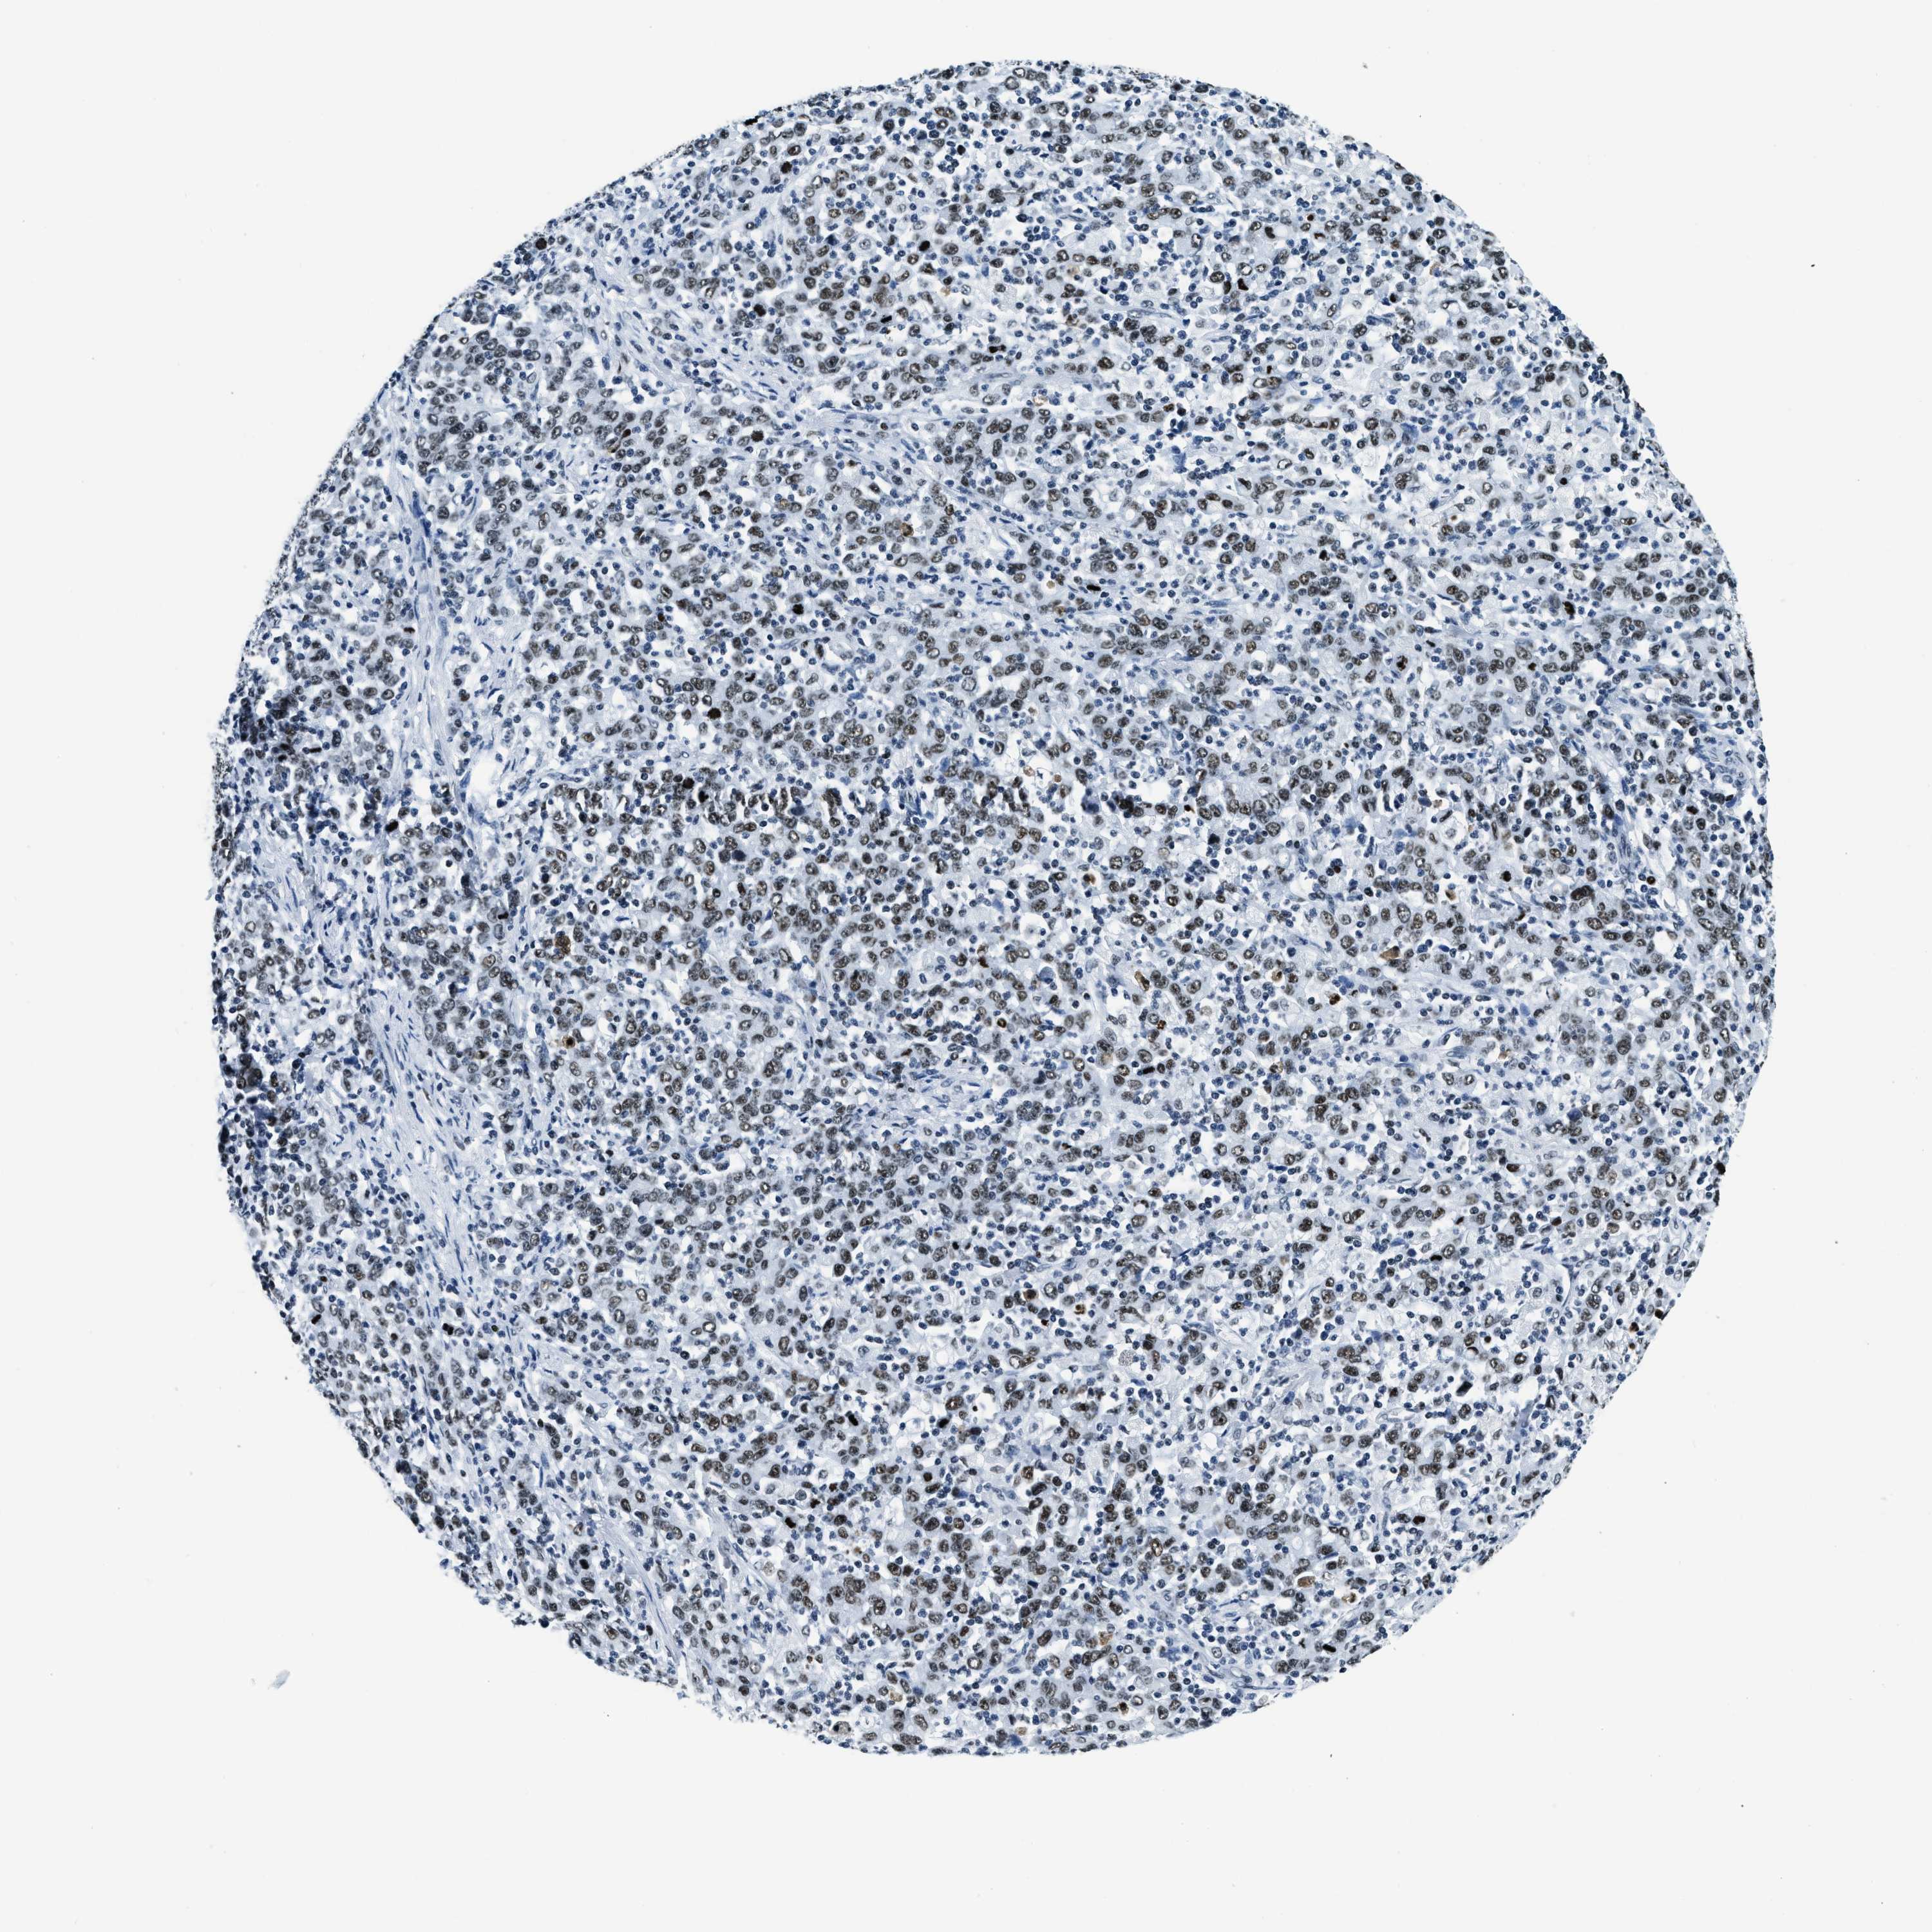

STOMACH CANCER - Protein expressioni

A mouse-over function shows sample information and annotation data. Click on an image to view it in a full screen mode. Samples can be filtered based on level of antibody staining by selecting one or several of the following categories: high, medium, low and not detected. The assay and annotation is described here.

Note that samples used for immunohistochemistry by the Human Protein Atlas do not correspond to samples in the TCGA dataset.

Antibody stainingi

Antibody staining in the annotated cell types in the current human tissue is reported as not detected, low, medium, or high, based on conventional immunohistochemistry profiling in selected tissues. This score is based on the combination of the staining intensity and fraction of stained cells.

Each image is clickable and will lead to virtual microscopy that enables deeper exploration of all samples and also displays staining intensity scores, fraction scores and subcellular localization as well as patient and tissue information for each sample.

Antibody HPA019039

Antibody CAB009058

Staining

High

Medium

Low

Not detected

Intensity

Strong

Moderate

Weak

Negative

Quantity

>75%

75%-25%

<25%

None

Location

Nuclear

Cytoplasmic/membranous

Cytoplasmic/membranous,nuclear

Adenocarcinoma, NOS